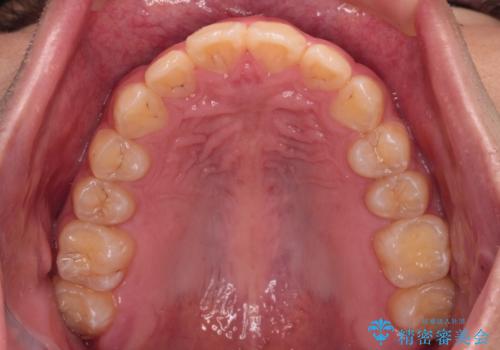

インビザラインで難儀する部分をワイヤー装置にて確実に改善しておくことで、インビザラインのみで行うよりも治療期間を短縮するとともに、より理想的な歯列に近づけて仕上げることができました。